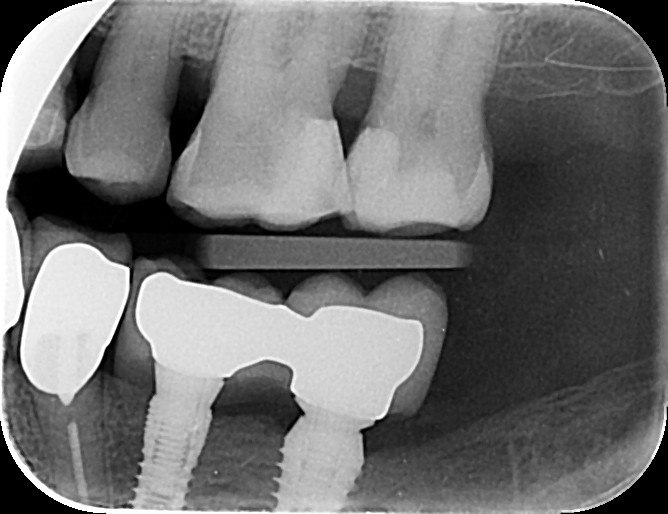

2. What option can be selected regarding the implant seen in this X ray?